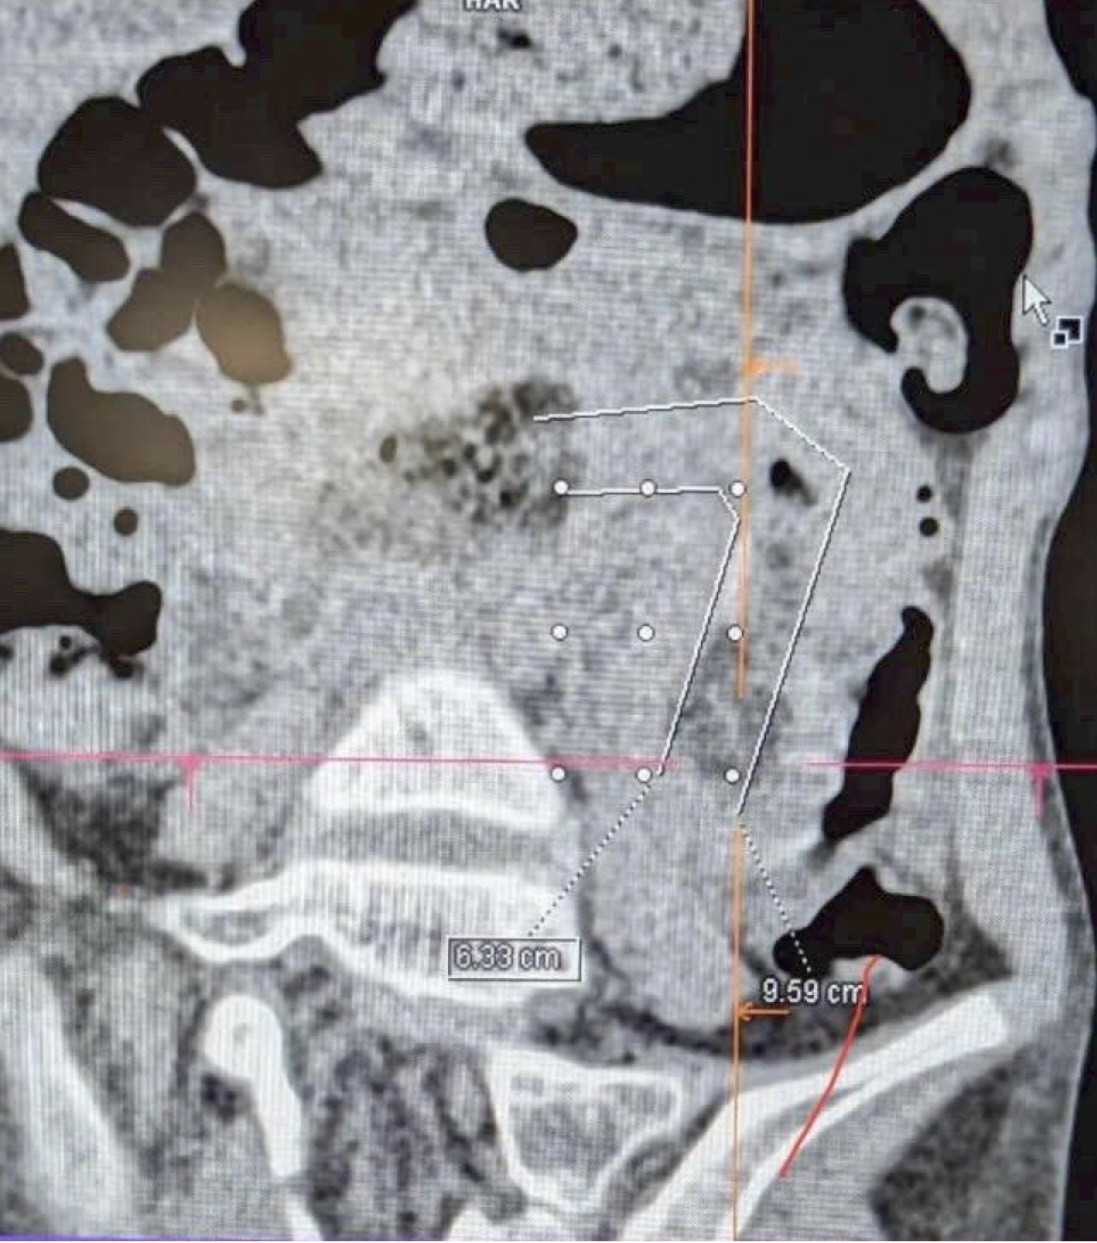

A CT scan showed a dense, rope-like mass of hair completely obstructing the digestive tract. The hairball extended from the stomach to the small intestine, causing a full blockage.

Doctors at FV Hospital deemed this an extremely rare and complicated case due to the size and density of the hairball, which spanned multiple segments of the intestine. If not handled properly, the risk of intestinal necrosis and life-threatening complications would have been high.

After careful evaluation, the surgical team opted to combine two minimally invasive techniques: gastrointestinal endoscopy from above and laparoscopic abdominal surgery from below. The endoscope helped pinpoint the location and guide the extraction from the stomach, while the laparoscopic procedure allowed access to the obstructed intestine.

Thanks to the coordination between the two surgical teams, the hairball was successfully removed after about three hours, fully resolving the blockage without damaging the intestines.